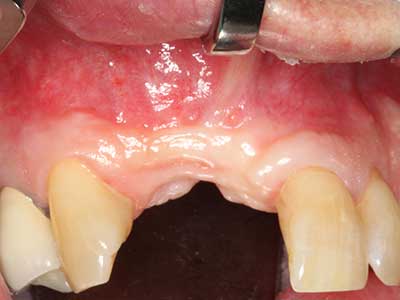

Si es preciso realizar intervenciones quirúrgicas en las que el hueso está en contacto directo con estructuras sensibles, como son los vasos sanguíneos o los nervios, los instrumentos rotativos presentan un enorme potencial de provocar lesiones iatrogénicas. Así, precisamente en la representación de nervios después de una lesión iatrogénica, o en el transcurso de la lateralización de un nervio para resecciones, reconstrucciones o incorporación de implantes, los equipos piezoeléctricos pueden resultar muy útiles para preparar la tapa ósea y retirar las partes de tejido duro cercanas al nervio (fig. 17-20). Por lo general, un ligero contacto del cordón nervioso con el inserto piezoeléctrico no tiene consecuencia alguna; ahora bien, un procedimiento poco cuidadoso con movimientos tipo sierra o piezas de trabajo sobre la base ósea aún existente puede provocar lesiones nerviosas temporales o incluso permanentes. Con todo, el riesgo de sufrir una lesión de este tipo se considera significativamente inferior que en los casos en los que se utilizan sierras y fresas (Pereira, Gealh et al. 2014).

Aplicación: Terapia periodontal